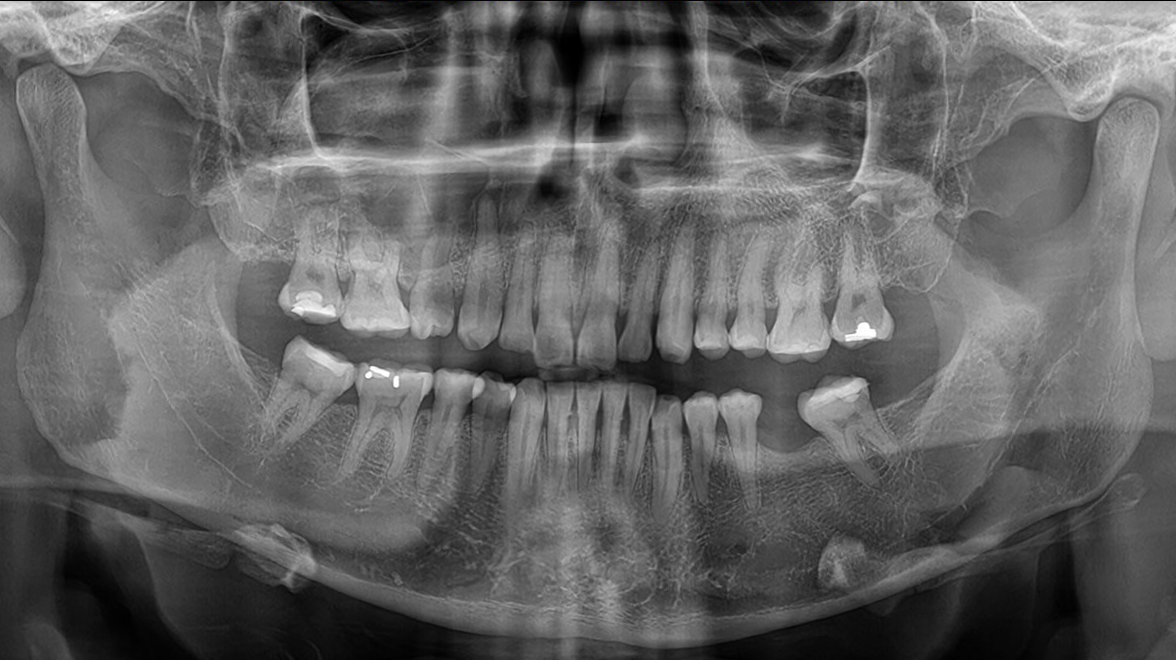

Paciente de sexo masculino de 12 años de dad con asimetría facial, refiere molestias en dientes (maxilar superior derecho) desde hace 5 meses. Antecedente de haberse golpeado y fracturado incisivo central derecho Al examen clínico se aprecia aumento de volumen en región geniana, intraoralmente a la palpación se aprecia claramente en zona vestibular abultamiento duro pero a distal de la lesión se torna blando sin crepitación. Persistencia en boca del canino temporal y ausencia clínica del canino permanente. El examen radiográfico muestra extensa imagen radiolúcida localizada en el maxilar superior derecho,en relación al canino impactado desplazado hacia distal y hacia vestibular, de bordes definidos con desplazamiento de la tabla vestibular.

El Quiste dentígero, es un quiste odontógeno que se desarrolla alrededor de la corona de un diente impactado, normalmente no envuelve a la raíz. Es el segundo quiste más frecuente (el primero es el quiste radicular). En la radiografía se observa como una imagen radiolúcida alrededor de la corona de un diente no erupcionado, de bordes corticados, indicativa de crecimiento lento y uniforme, puede ser unilocular o multilocular, generalmente desplaza al diente en cualquier dirección. Puede llegar a ser tan grande y producir «expansión»; de corticales frecuentemente de la tabla ósea vestibular. Si se localiza próximo al seno maxilar puede expandirlo, llenarlo o desplazarlo. Cabe recordar que los bordes corticados de la lesión podrían perderse si existiese un proceso infeccioso sobreagregado.